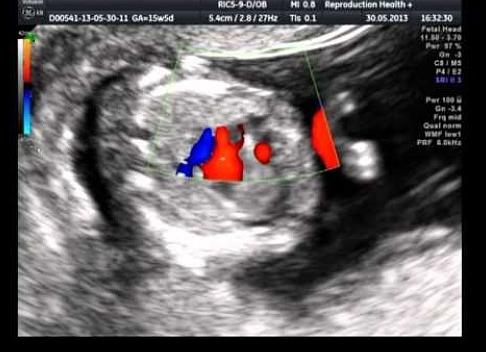

Плодное яйцо без эмбриона часто довольно диагностируется в матке даже у совсем здоровых и молодых женщин. Какова причина данной лечится, патологии ли это, как избежать такого замершей рода беременности?